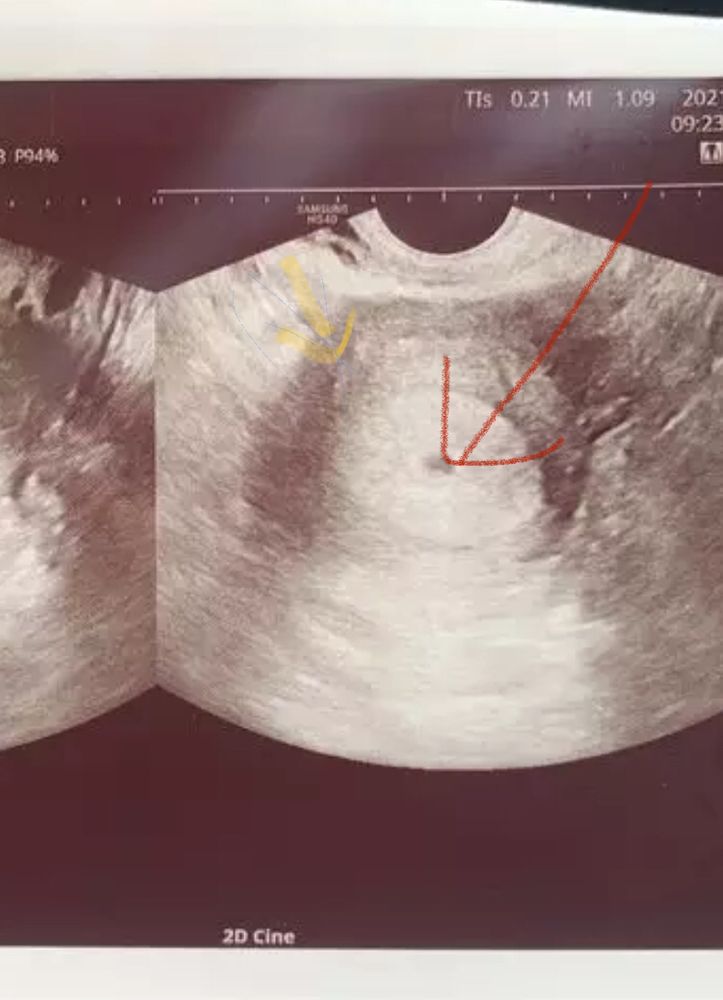

Девочки всем привет.Что думаете насчёт фото. Врач толком ничего не сказал только что придти через неделю на повторное узи посмотреть растет кроха или нет.Тянул немного живот с 21-23.06 но потом перестал.Грудь чувствительна как перед месячными но прям вот что бы болела нет такого,в целом чувствую себя хорошо.Эта первая беременность за 7лет ожидания,переживаю немного по мелочам.Врачь даже не сказал маточная или не маточная Б.Вот снова ожидания .Последние М были 18.05 овуляция была 31.05(отследила по тестам) Тест на Б сделала 21.06 на узи была 28.06.Что скажите?)

Похоже на маточную,но срок не соответствует,если вы говорите овуляция была 31.05 то 29.06 на момент УЗИ было 29 дпо,это срок 6 недель

Я не медик но вроде как плодное яйцо в матке и беременность маточная )

Если месячные были 18.05 то срок приблизительно 5-6 недель

Вот , красная стрелка плодное яйцо , желтая- матка

Ну вообще да , рано не информативно скажем так , через неделю уже должен эмбрион появится и возможно даже сердцебиение послушается)